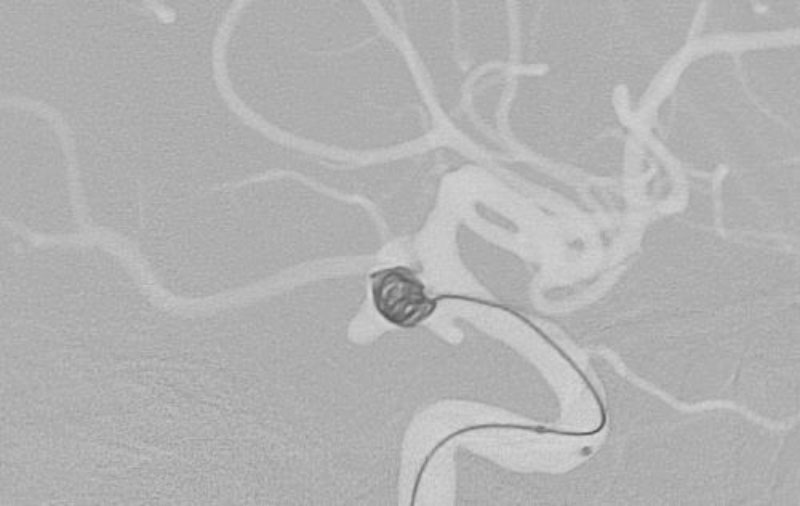

くも膜下出血

左中大脳動脈瘤破裂

40代

救急外来

No.1596 手術後